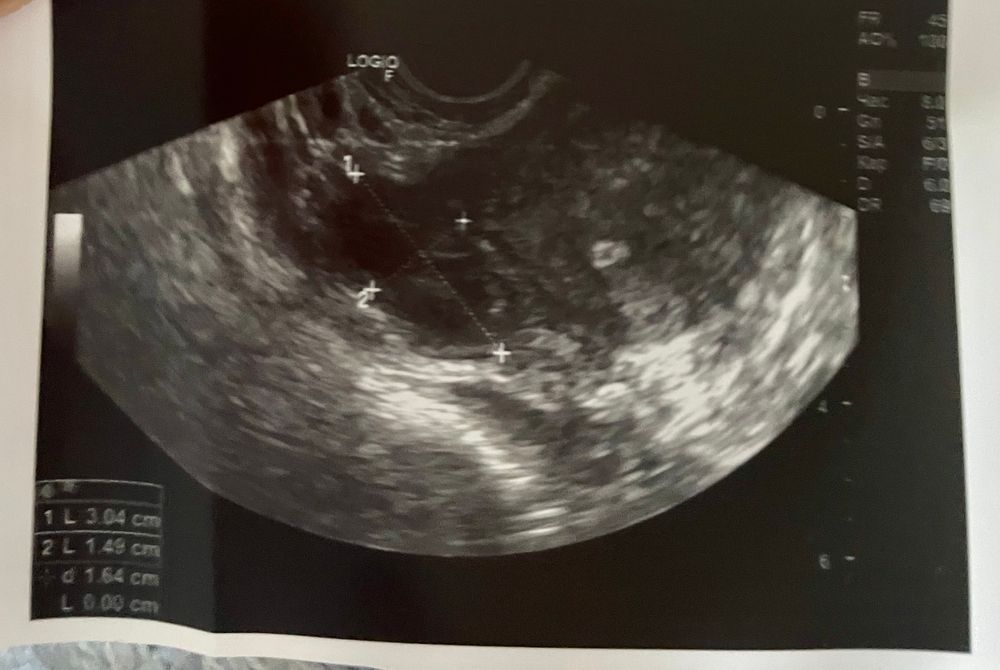

11 дц 🌟 тесть вроде поярче . В ля где то 17 мм, а в пя 21 мм .. разбудили мой правый яичник ). Новогодние праздники 🎄 пью ))) овуляция пролетная 😎 вечерний тест почти положительный 😔 эх овуляция справа🥺 тут все сложилось и муж дома и овуляцию поймала) но не с той стороны 😥😥😥